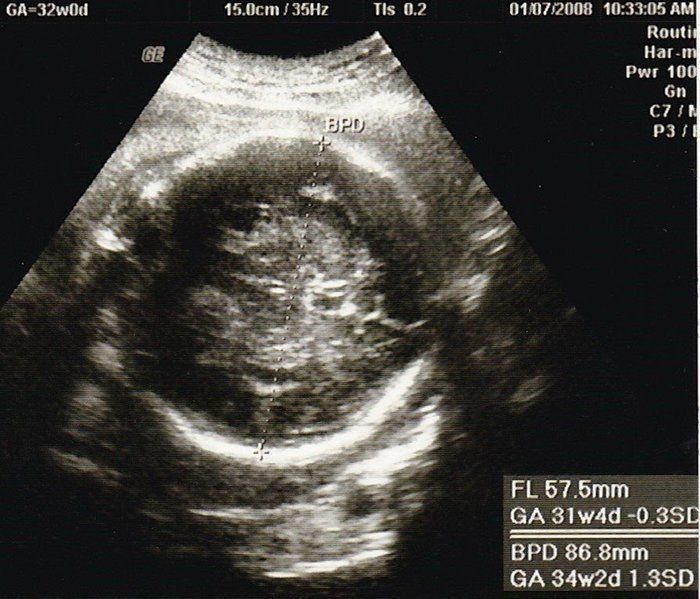

小吉さんの妊娠32週目のエコー写真

思いがけず授かった2人目は43歳の高齢出産!健診は不安と期待との板挟み!

赤ちゃんの背骨と肋骨がしっかりとできていることが確認できました。「小さいのにちゃんとあるな、頑張っているな」と感動したのを覚えています。